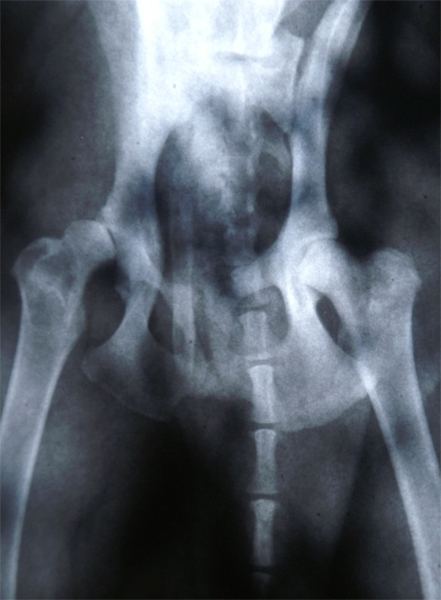

Inmiddels, ruim twee jaar verder, mag ik wel in mijn handen klappen, want hij heeft klaarblijkelijk de allerlichste vorm van HD die er bestaat. Ook de laatste röntgenfoto in oktober toonde weer aan dat er nog steeds geen verschil is met de eerste. Maar nu. Hoe vaak zeggen mensen wel niet: "met HD zo laten spelen, dat zou ik nooit toelaten" of "een HD-hond moet rustig aan de lijn blijven" of "wil je soms dat hij meer pijn krijgt?". Enzovoorts....